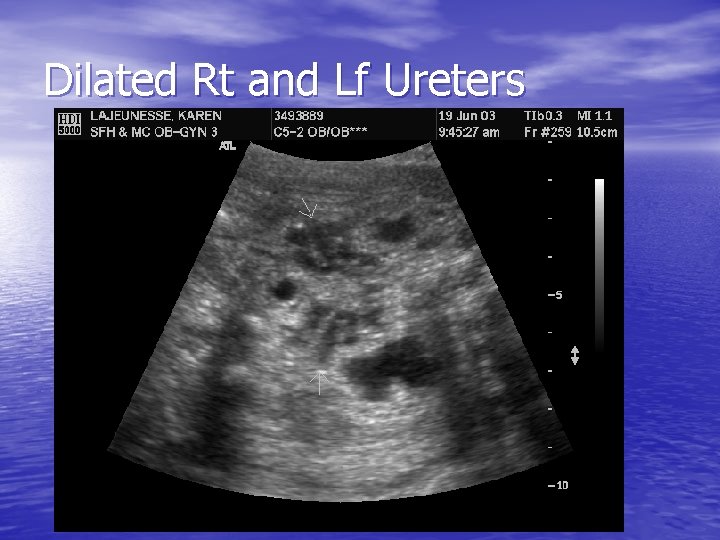

Dilated Rt and Lf Ureters

PUVS - Findings • Elevated intravesicular pressures leading to reflux to ureters and renal pelvises • Hydronephrosis develops from continued urine production with obstruction • Renal pelvis and calyceal systems become distended, compress renal parenchyma

PUVS - Findings • Histologically – Smooth muscle hypertrophy and • • hyperplasia within the bladder wall – increased bundle of smooth muscle Dilation of distal and proximal tubules associated with peritubular and interstitial fibrosis Fibrosis = echogenic appearance of the renal parenchyma on ultrasound